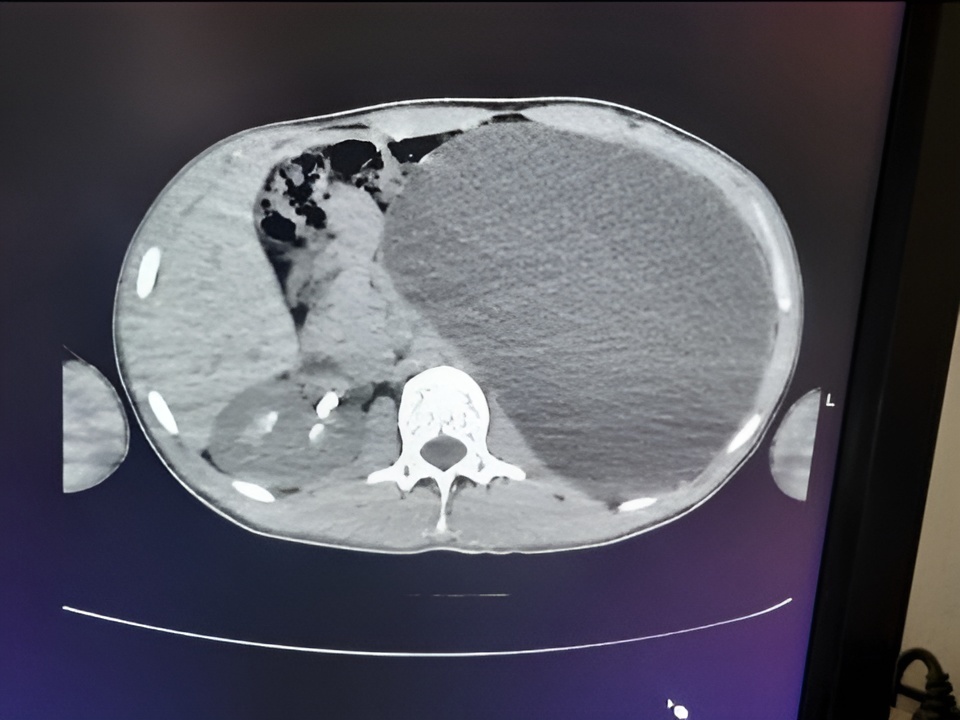

Во время УЗИ на профосмотре перед трудоустройством врачи обнаружили у 17-летнего жителя Новосибирска гидронефроз почки — критическое состояние, которое в любой момент могло привести к летальному исходу, сообщает пресс-служба регионального Минздрава.

Юноша чувствовал себя абсолютно здоровым и никогда не предъявлял жалоб на мочевыделительную систему. Однако диагностика выявила страшную патологию: почка пациента достигла размеров пятилитровой бутылки и занимала практически всю брюшную полость, сдавливая соседние органы.

«Это была настоящая бомба замедленного действия, — подчеркнули в пресс-службе Детской городской клинической больницы № 1. — Любая травма, неосторожный удар в живот — и орган мог разорваться, что привело бы к внутреннему кровотечению и гибели пациента».

Хирурги провели экстренную операцию. Через четыре миниатюрных прокола врачи эвакуировали скопившуюся жидкость, после чего удалили необратимо поврежденную почку. В настоящее время пациент чувствует себя удовлетворительно и идет на поправку.